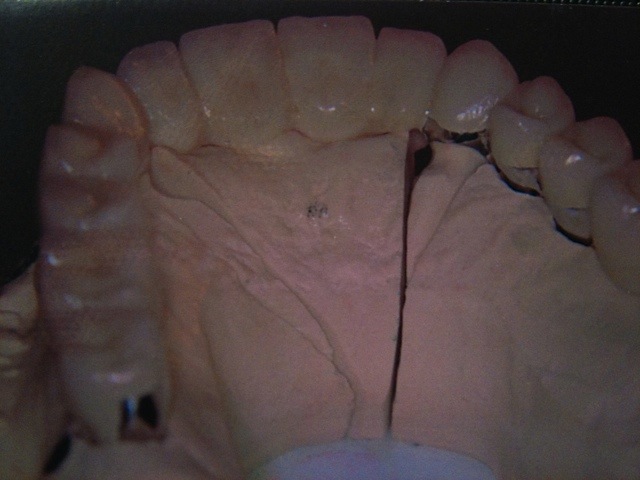

Komplett-Implantation: